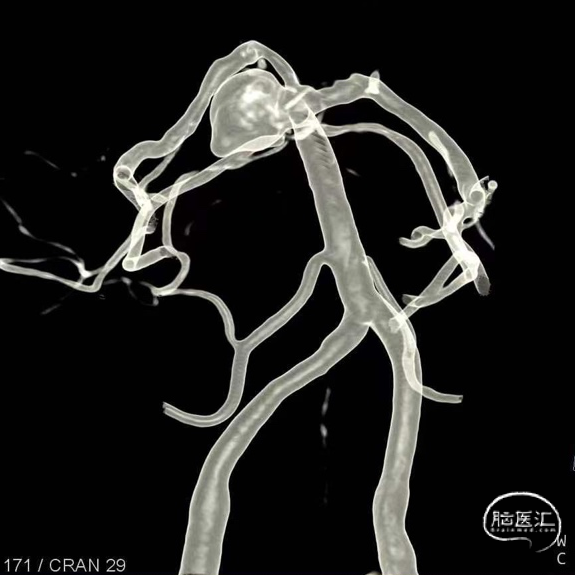

6.右侧颈内动脉C7段、左侧大脑中动脉M1段、基底动脉末端动脉瘤

动脉瘤一:基底动脉末端动脉瘤

(小脑上动脉瘤,侧壁)

动脉瘤一:基底动脉末端动脉瘤,由左侧大脑后动脉与左侧小脑上动脉瘤夹角处动脉瘤形成且为不规则状;瘤体上有子囊形成,左侧小脑上动脉从近心端瘤颈处动脉瘤瘤体上发出,动脉瘤与载瘤动脉近直角。

经测量可得动脉瘤宽度平均值为8.88mm,动脉瘤最小高度为7.71mm,瘤颈约为4.03mm。参考尺寸选择表,选择WEB™ SL 10*5,VIA™ 33微导管。

此为左侧大脑中动脉瘤,近端血管极为迂曲,瘤体有突出的子囊,动脉瘤与载瘤动脉有一定夹角,动脉瘤呈上窄下宽形状,M2段下干从瘤颈近端发出。

动脉瘤平均宽度5.41mm, 最小高度为3.71mm,瘤颈约为4.94mm,使用WEB™ SL 6*3mm瘤内扰流装置进行栓塞治疗。

右侧后交通段动脉瘤,大小约13.36mm*13.26mm,瘤体上有子囊形成,床突段至后交通段血管稍狭窄,脉络膜前动脉距瘤颈部有一定距离。